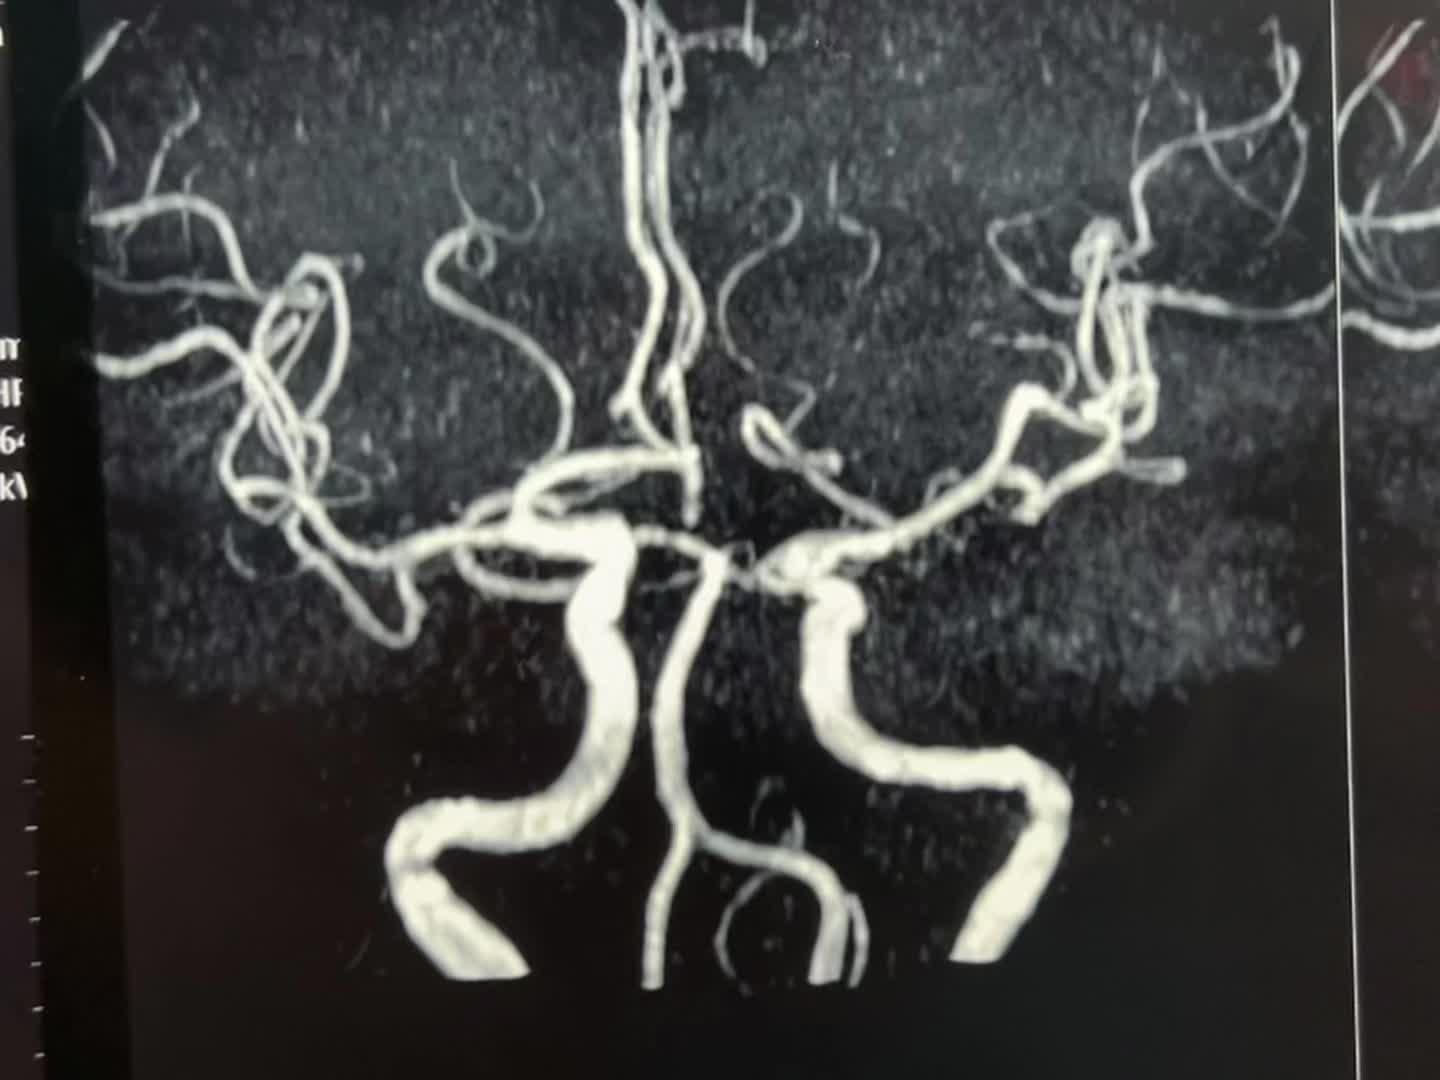

一天两个颅咽管瘤手术医生是很辛苦的 今天按计划作了两个颅咽管瘤手术。这是第二个病人,云南省文山州的警察,因记忆力差、爱睡觉、视力下降到医院检查发现了颅咽管瘤,是乳头型颅咽管瘤。 今天晚上九点多钟颅咽管瘤完全切除了,同时发现前交通动脉有个小动脉瘤,征得家人同意后作了动脉瘤夹闭术。期望病人一切都好!